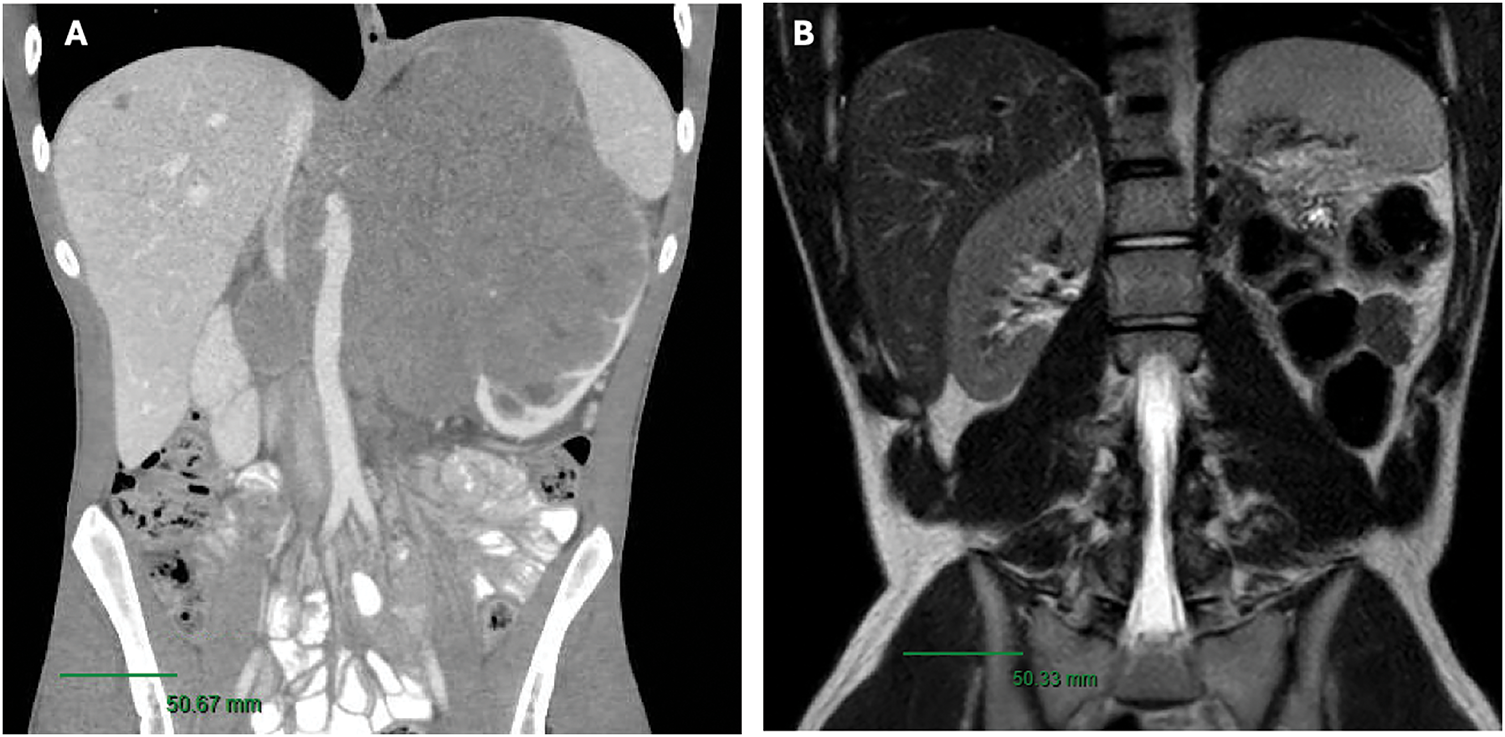

Remarkably, surgical pathology revealed no residual carcinoma, only markedly atrophic renal parenchyma with extensive treatment effects (fibrosis), along with negative margins and lymph nodes. Given the pathology findings, a decision was made not to re-initiate systemic therapy at that time and to monitor with imaging. Follow-up magnetic resonance imaging (MRI) 4 months postoperatively revealed no evidence of residual or recurrent malignancy in the surgical bed, including a stable 4 mm hepatic lesion adjacent to the gallbladder fossa, which remained unchanged on a subsequent MRI follow-up 9 months postoperatively (Figure 1). A chest CT at 9 months postoperatively also showed no evidence of disease.

FIGURE 1. (A) Pre-treatment CT Scan (B) Post-left radical nephrectomy MRI/pelvis revealing no suspicious masses or abdomen evidence of recurrence within the nephrectomy bed. Scale bar, 50 mm

His case was discussed at the Genitourinary Tumor Board for assessment of his persistent hepatic lesion, and a multidisciplinary evaluation concluded that the lesion was likely scar tissue; thus, no further treatment was pursued. At the time of the last follow-up, 44 months postoperatively, he continued to do well and remains on surveillance, with no evidence of disease on repeat chest CT and abdominal MRI, and no residual liver lesion identified.